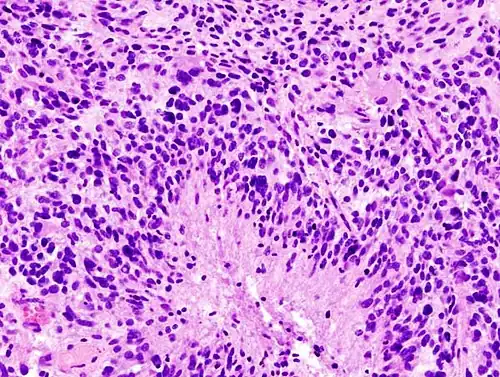

-

Histopathology of glioblastoma, showing high grade astrocytoma features of marked nuclear pleomorphism, multiple mitoses (one at white arrow) and multinucleated cells (one at black arrow), with cells having a patternless arrangement in a pink fibrillary background on H&E stain. -

Lower magnification histopathology, showing necrosis surrounded by pseudopalisades of tumor cells, conferring a diagnosis of glioblastoma rather than anaplastic astrocytoma